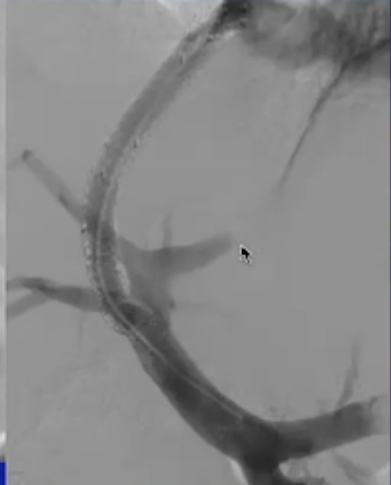

伴有腹痛及肠道缺血的情况 使用抗凝剂治疗后,大多数患者会有所好转,但有 10% - 20% 的患者治疗无效。 对于这些患者,应进行经皮经肝的血栓性门静脉(PV)穿刺、溶解、抗凝治疗,通常效果是足够的,越早发现病情越好。 经颈静脉的通路不建议作为首选方法,因为接受溶栓治疗的患者其并发症风险较高。 使用 t-PA 治疗后,肝内血流情况良好,且可见外周门静脉分支血管,继续使用 t-PA,并进行抗凝治疗。

急性门静脉血栓的TIPS

为那些对溶栓治疗反应不佳的患者预留床位

这些患者通常就诊较晚,且诊断有误,其肝脏发展为肝硬化的可能性很大。 经颈静脉肝内门体分流术(TIPS)能够维持或促进门静脉系统和脾静脉系统的通畅。 采用初始的经皮穿刺途径有助于实现 TIPS 手术。(初始经皮经肝导管作为门静脉穿刺标记) 门静脉与体循环之间的压力差有助于做出这一决定,但在没有血流情况明确的情况下,其准确性存疑。

急性病例,已有肠道缺血的迹象,经皮穿刺入路,尿激酶溶栓(t-PA),血流不畅,转为经颈静脉肝内门体分流术(TIPS),抗凝治疗

从技术层面来讲,要准确击中“PV 锁定点”并非易事,这个点的位置比预期的要靠后,需要使用斜位来瞄准发力。